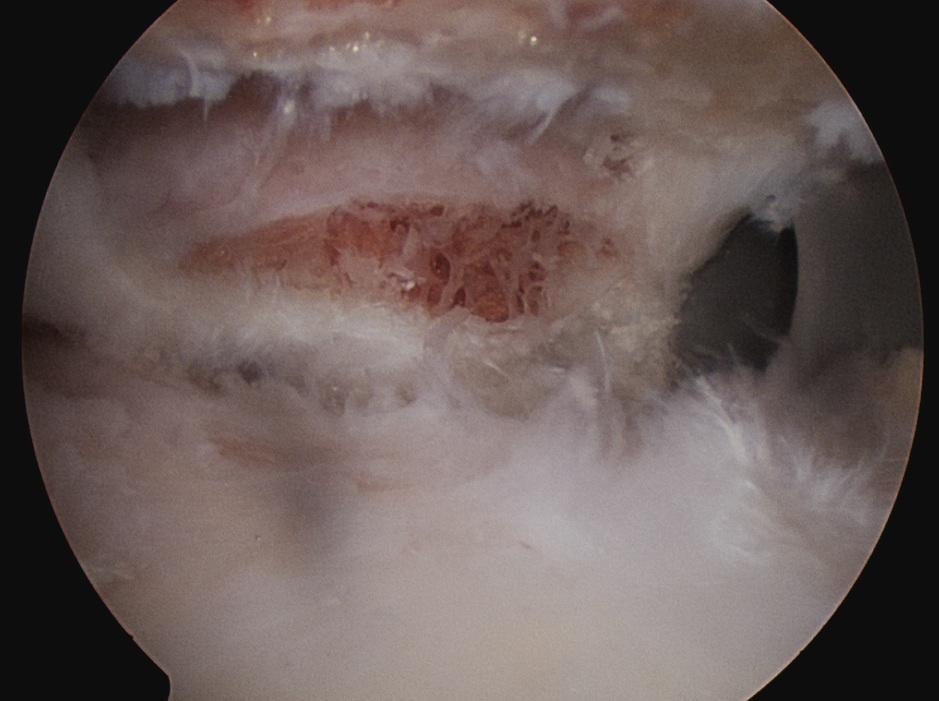

Technique

1. Identify distal clavicle

- camera posterior portal, electrocautery lateral portal

- remove bursa in subacromial space

- follow anterior acromion medially with cautery

- identify the distal clavicle (push down on clavicle repetitively)

- clean and identify clavicle anterior and posterior

2. Anterior portal

- placed just at lateral aspect of distal acromion

- in line with AC joint

- remove anterior then posterior clavicle

- must remove full thickness of distal clavicle superiorly / be able to visualise superior AC ligament

- must not leave posterior edge

- can place camera in lateral portal to enhance view